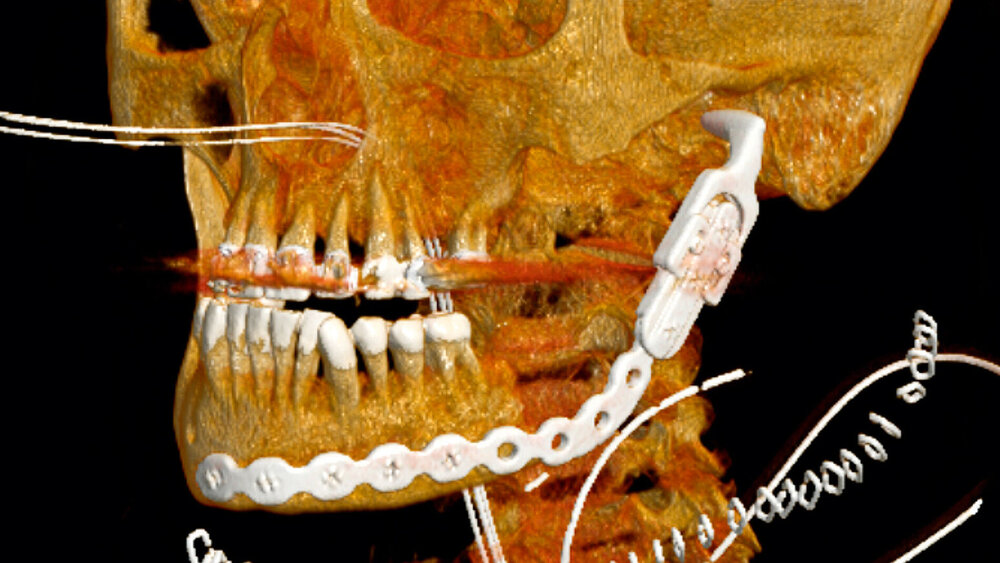

Zunächst erfolgte in Lokalanästhesie die Spaltung des paramandibulären Infiltrats von intraoral mit Spülung und Streifeneinlage. Anschließend wurde die Patientin zur Schmerz- und systemischen Antibiotikatherapie (Ampicillin/Sulbactam) stationär aufgenommen. Im DVT bestätigte sich der anfängliche Verdacht auf ein in regio 038 befindliches Zahnfragment (Abbildung 1). Aufgrund der Lage des Fragments, der starken Schmerzen und des reduzierten Allgemeinzustands der Patientin erfolgte die Entfernung des verlagerten und ankylosierten Zahnfragments in regio 038 in Vollnarkose.

In Vollnarkose erfolgte von extraoral die Einlage eines weiteren Röhrchens in Richtung links submandibulär-anterior sowie eine gründliche Revision der intraoralen Wunden. Dabei kam es bei der intraoralen Inspektion und Wundrevision zu einer pathologischen Kieferwinkelfraktur. Es bestätigte sich die bereits in der CT-Bildgebung diagnostizierte, ausgeprägte osteolytische Veränderung des Unterkieferknochens. Die Fraktur wurde zunächst temporär mittels einer 2.0-Mini-Osteosyntheseplatte fixiert (Abbildung 3).